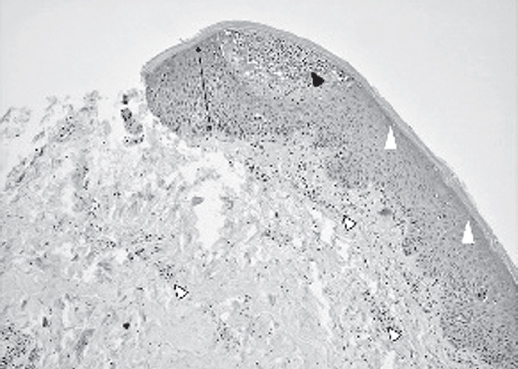

Psoriasis is a chronic immune-associated skin disease of a multifactorial nature with phenotypic diversity in the general population, as well as a large number of comorbid diseases in patients. The generalized pustular psoriasis, historically was considered one of the variants of the course of psoriasis. Today some authors classify it as a genetically different condition combined with a plaque psoriasis. The selected tactics of psoriasis therapy can become a trigger for the manifestation of a pustular form. Despite the availability of modern data on the immunopathogenesis of the disease, there are no standardized methods of treatment that can take into account the individual characteristics of patients, which is doubly important in pediatric practice, since the arsenal of drugs approved for use is limited. We demonstrate the clinical case of a patient with progressive plaque psoriasis, earlier getting systemic and topical corticosteroids for a long time. This therapy did not allowed to take the course of the disease under control, even more it caused appearance of complications. Our clinical example from practice allows us to focus on the problem of complications of classical therapy for psoriasis and the intricacies of prescribing both topical and systemic drugs. Systemic therapy requires the development of algorithms based on objective diagnostic criteria and the results of studies on the effectiveness and safety of modern drugs in pediatric practice.